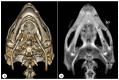

Anatomical Description of Loggerhead Turtle (Caretta caretta) and Green Iguana (Iguana iguana) Skull by Three-Dimensional Computed Tomography Reconstruction and Maximum Intensity Projection Images

The growing interest in reptiles has posed a challenge to veterinary clinicians due to the lack of a standardized system to perform anatomical studies similar to those used for dogs and cats. In this paper, we have attempted to describe, employing computed tomography and subsequent three-dimensional reconstructions, the normal anatomical features that comprise the skulls of two species of reptiles: the loggerhead turtle (Caretta caretta) and the green iguana (Iguana iguana). Computed tomography (CT) and subsequent image processing allowed the identification of the bony structures that comprise the head of these species. As a result, and based on previous articles, we propose the most significant anatomical differences and similarities between these species.